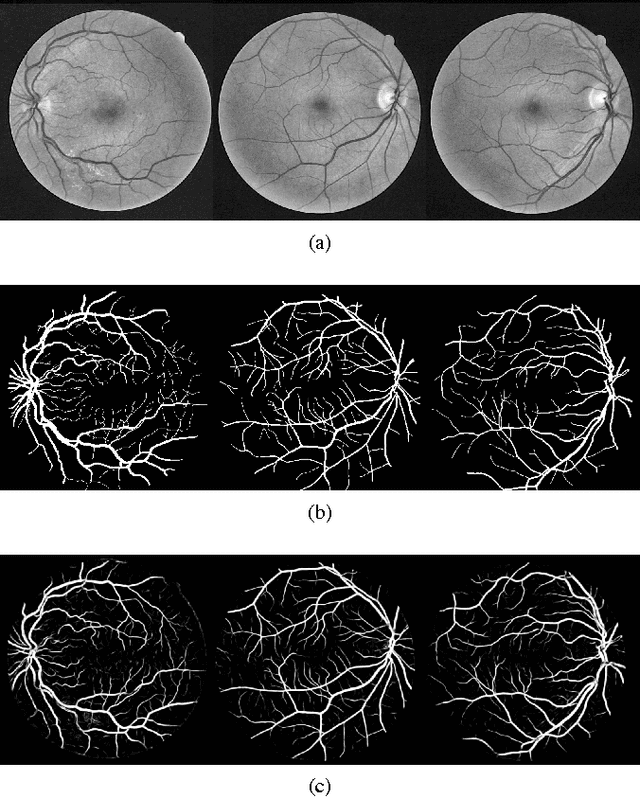

Abstract:Automatic segmentation of retinal blood vessels from fundus images plays an important role in the computer aided diagnosis of retinal diseases. The task of blood vessel segmentation is challenging due to the extreme variations in morphology of the vessels against noisy background. In this paper, we formulate the segmentation task as a multi-label inference task and utilize the implicit advantages of the combination of convolutional neural networks and structured prediction. Our proposed convolutional neural network based model achieves strong performance and significantly outperforms the state-of-the-art for automatic retinal blood vessel segmentation on DRIVE dataset with 95.33% accuracy and 0.974 AUC score.